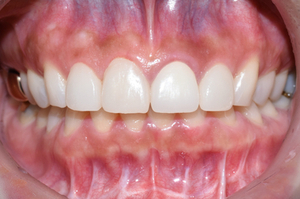

라미네이트는 본 뜬지 일주일 후에 완성이 되어 붙였으며

라미네이트 붙이고 일주일 후 촬영한 사진

치료 받은 4개의 앞니가 위와 같이 시원하고 하얗게 보이는 치아로 완성되었습니다.

모양 자체도 그 전의 마름모꼴의 치아보다 훨씬 개선이 된 것을 볼 수 있습니다.